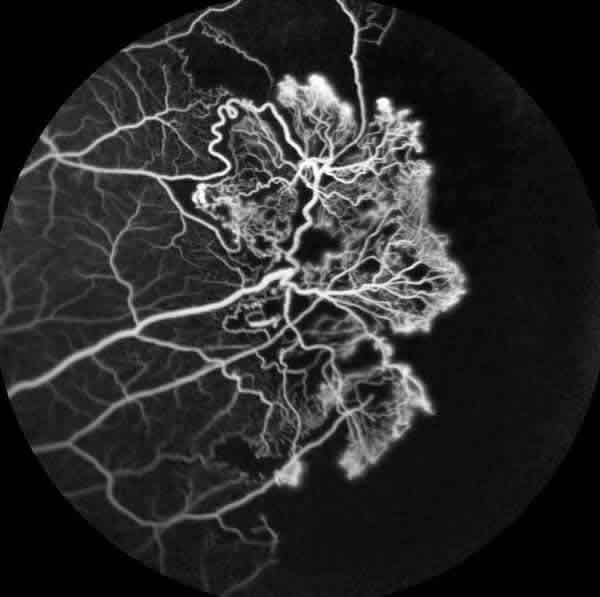

En la exploración oftalmológica la agudeza visual mejor corregida (AVMC) era de 0,6 en ambos ojos (AO). Por biomicroscopía anterior se apreciaba muy leve tortuosidad de los vasos conjuntivales, sin atrofia iridiana (fig. 1). La tonometría era de 16 mmHg. AO La funduscopía de ojo derecho (OD) mostraba oclusiones vasculares en la periferia 360 grados, con terminación muy abrupta de los mismos, telangiectasias, anastomosis arteriovenosas, zonas de no perfusión capilar, vasos hialinizados (fig. 2). El ojo izquierdo (OI) presentaba además de las lesiones descritas en el OD, neovasos muy llamativo en «abanico» en la zona temporal superior y blanco sin presión en la periferia nasal (fig. 3).

Fig. 2: Funduscopía ojo derecho donde se aprecian áreas de oclusión capilar y shunt arteriovenosos.

La angiofluoresceingrafía (fig. 4) evidenció una gran isquemia periférica y los neovasos del OI (fig. 5) pero sin isquemia macular. La tomografía de coherencia óptica tampoco demostró alteraciones foveales.

Fig. 4: Angiofluoresceingrafía con extensas áreas de no perfusión capilar periférica en ojo derecho.